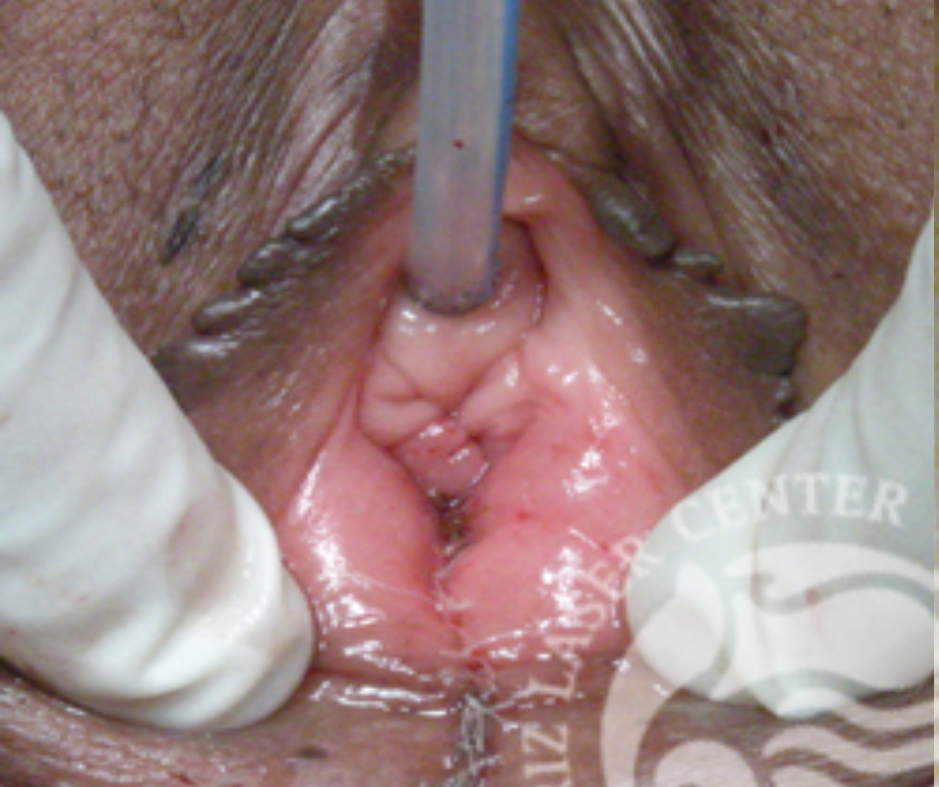

나이 : 39 / 출산경력 : 2 / 이름 : 정OO

레이저질성형수술  LVR™(Laser Vaginal Rejuvenation™)

- Before : 출산 경험과 노화 등으로 질 내부의 이완정도가 심해 외부에서도 쉽게 질 내가 벌어진 것을 확인할 수 있음

- After :   LVR 수술 후 늘어진 회음부가 당겨 올라 좁아졌고 질 안쪽도 구조가 바뀌어 질 내외부가 빈틈없이 닫혀진 모습.